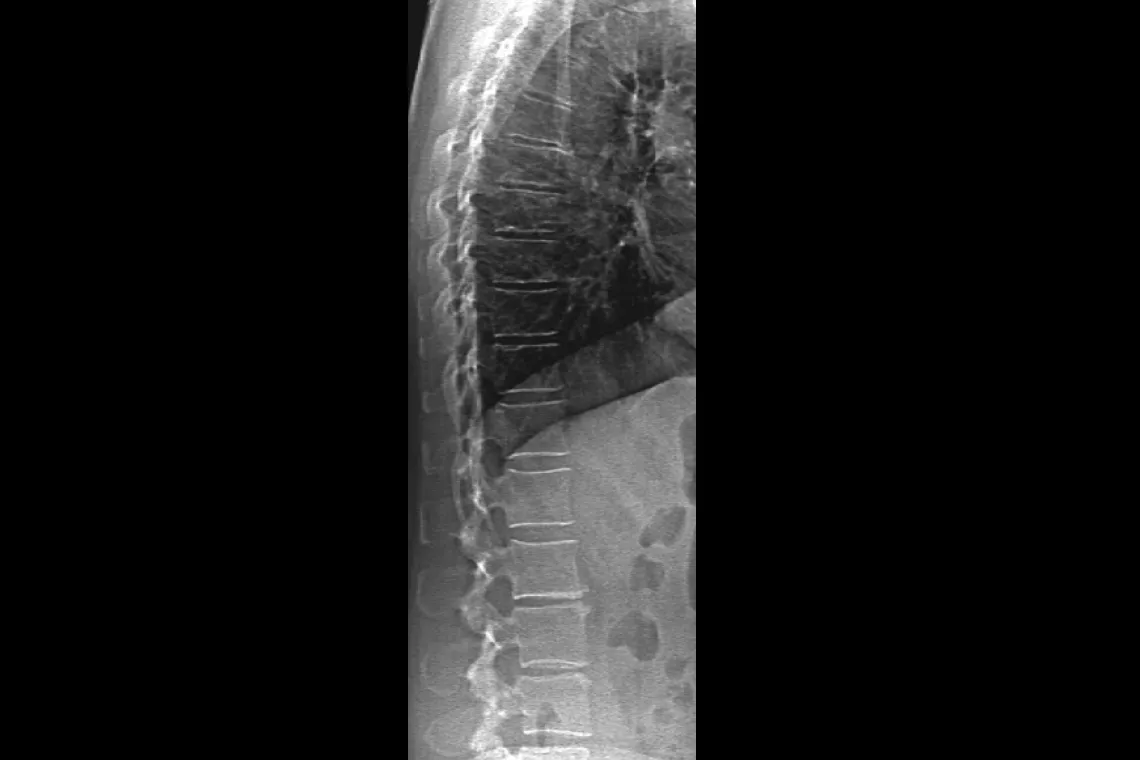

O Horizon DXA gera imagens de qualidade radiográfica de todo o fémur para a avaliação de potenciais fraturas atípicas do fémur.31 Uma radiografia rápida de 15 segundos revela um espessamento cortical do osso, fazendo com que seja fácil e rápido monitorizar os efeitos da terapia com bisfosfonatos ao longo do tempo.

Avalie o risco de fratura através da combinação de uma medição precisa da densidade óssea com imagens vertebrais de alta resolução. É possível identificar fraturas da coluna vertebral com uma imagem de baixa dose e energia única em 10 segundos.

Melhore a precisão e reduza os erros de análise pós-exame com a colocação precisa e assistida por software de espaços entre os discos vertebrais para análise gráfica.

O sistema de calibração dinâmica exclusivo da Hologic proporciona uma calibração pixel a pixel através de equivalentes de ossos e tecidos — para uma maior precisão a longo prazo.32

Um novo conjunto do detetor cerâmico de alta resolução digital é combinado com uma verdadeira geometria de aquisição de feixe de dupla energia em leque para permitir medições rápidas da densidade óssea num único exame. O OnePass elimina os erros de sobreposição do eixo e de distorção da imagem que se encontram nas técnicas de aquisição retilíneas — para uma qualidade de imagem superior e estabilidade dos dados. Mais um exclusivo da Hologic.